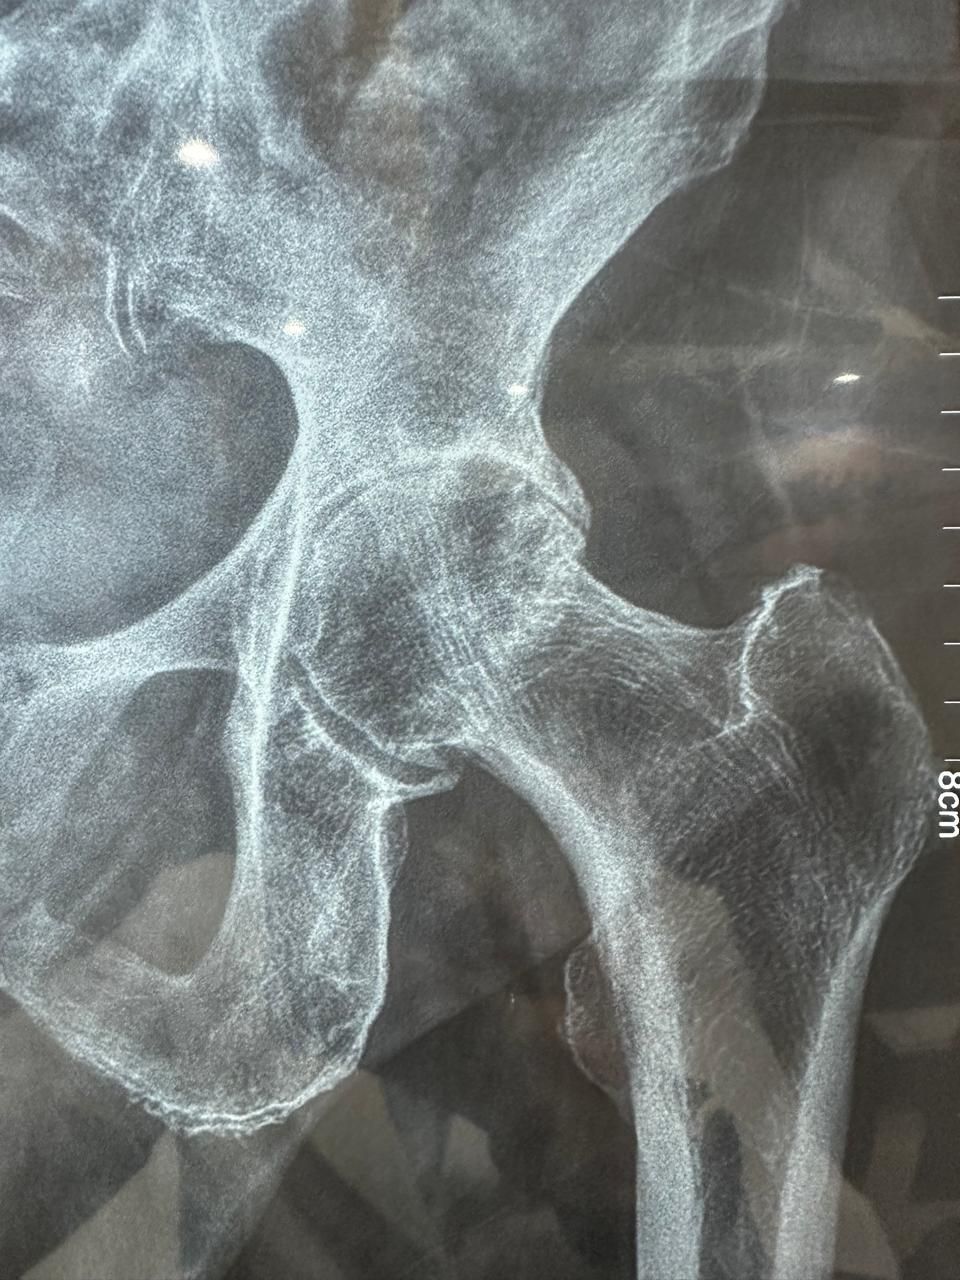

La ortopedia se enfoca en las enfermedades y alteraciones del sistema músculo-esquelético, tanto en adultos como en pacientes jóvenes. El Dr. Juan Carlos Torres Archila, especialista en ortopedia en Comitán, Chiapas, ofrece atención integral y personalizada para afecciones crónicas, degenerativas o congénitas que afectan huesos, articulaciones, músculos, tendones y ligamentos.

Cada caso es valorado a profundidad para proponer tratamientos conservadores (rehabilitación, ejercicios, ortesis) o procedimientos quirúrgicos cuando son necesarios, como artroplastías (colocación de prótesis articulares) o cirugías mínimamente invasivas como la artroscopía.